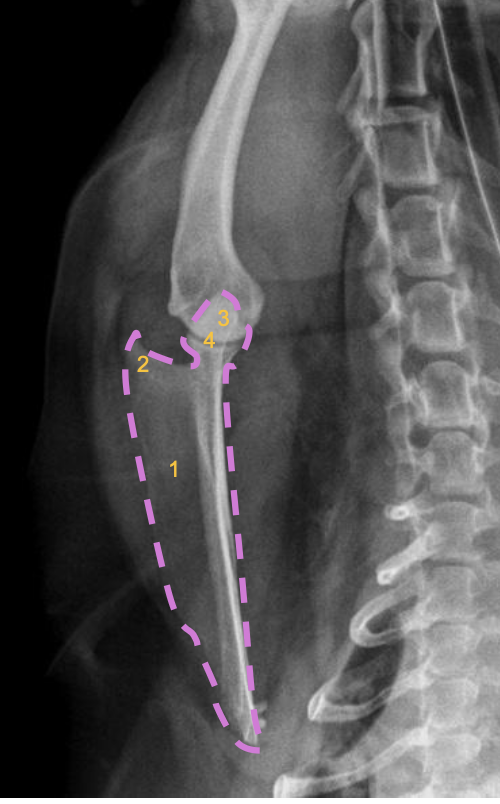

what radiographic view of the humerus is shown?

lateral view